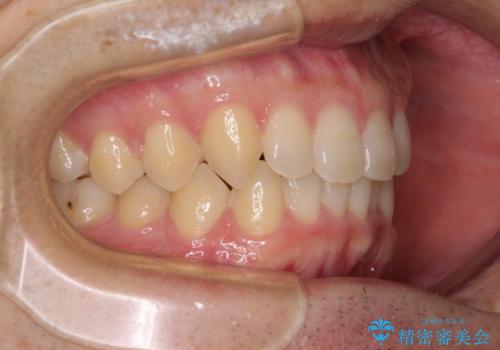

- 上下前歯のデコボコと深い咬み合わせを気にして来院された患者様です。

インビザラインによる上下歯列の拡大と、IPR(歯と歯の間を削る)にるスペースの獲得により、前歯のデコボコとディープバイトを改善することとしました。

もう少し下の前歯を整えたかったのですが、患者様の治療を早く終了させたいという希望により、細かい叢生を残しての終了となりました。